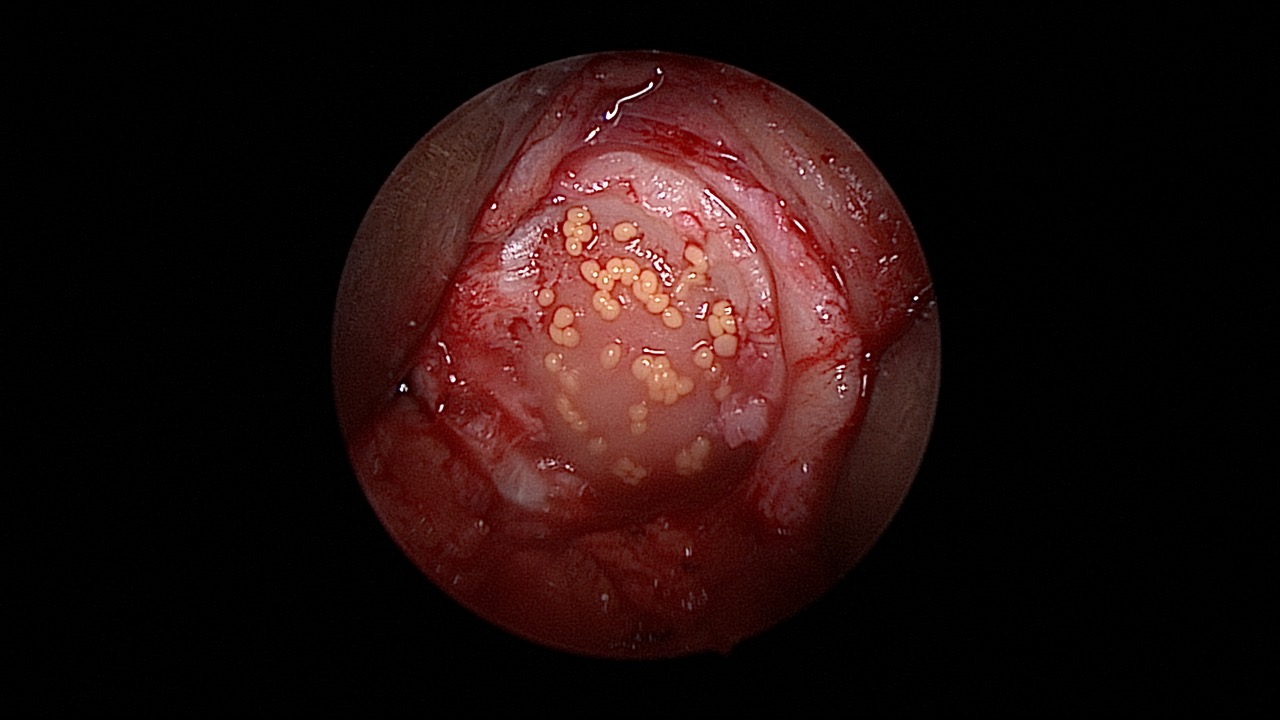

#052: Arthroskopischer Meniskusteilersatz

Operation und Kommentar: Dirk Holsten

Provided by

Winglet

Date

Sep 2019

Format

TechTip

Price

0.99 €

Arthroscopy

Joint Replacement

Knee